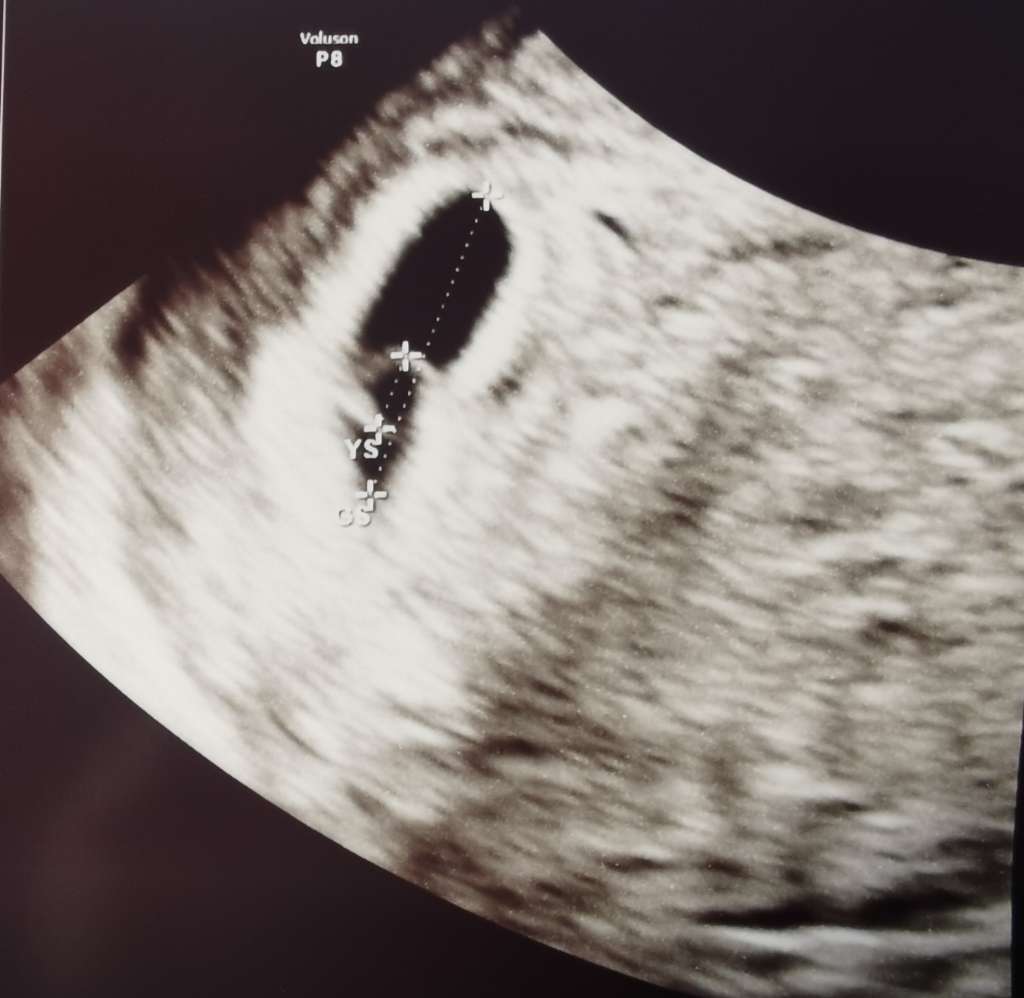

Wszytko jest w porządku. Lekarz potwierdził ciąże zarodek prawidłowy zagnieżdżony. Termin z OM pokrywa się z terminem z USG czyli 2 styczeń. Mam alej brać leki duphaston, luteina, acard i termin kolejnej wizyty 4 czerwiec. Jak weszłam do niego to cała się trzęsłam. Wrzucam zdjęcie małego lokatora